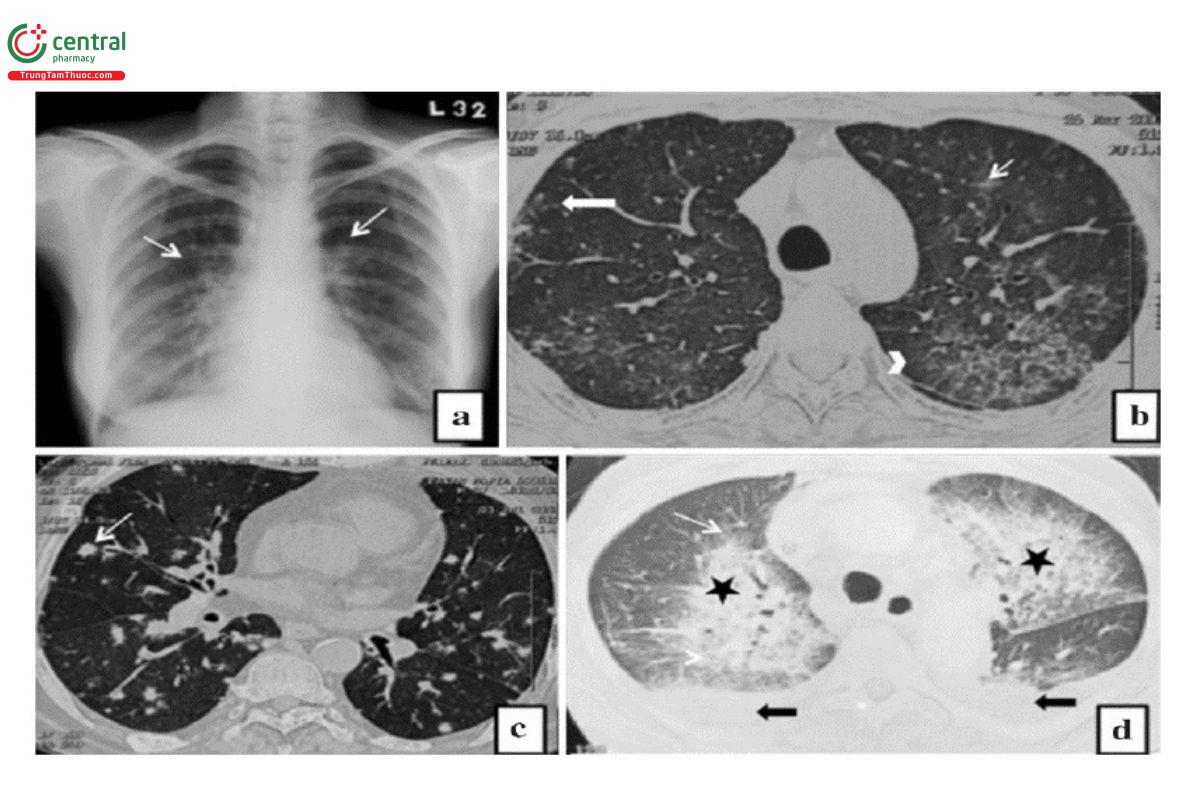

Viêm phổi do virus: Hình ảnh của viêm phổi do virus rất đa dạng, trong đó hình ảnh viêm phế quản - phổi và kính mờ chiếm ưu thế. Ở những bệnh nhân mức độ bệnh nhẹ, trên hình ảnh X-quang ngực có thể thường bình thường hoặc thấy phổi tăng kích thước ở cả hai bên với các dấu hiệu mờ đậm quanh mạch máu phế quản. Viêm phổi do Adenovirus và Influenzavirus thấy các vùng đông đặc thành đám hoặc thùy với các hình ảnh kính mờ và nốt quanh phế quản. Viêm phổi do Varicella zoster thường gặp các nốt phân bố ngẫu nhiên ở cả hai phổi [2, 6].

Hình 10. Hình ảnh viêm phổi do virus.

Chú thích: a) Hình ảnh các lưới mờ ở hai phổi chủ yếu ở quanh rốn phổi (mũi tên) với tăng kích thước các trường phổi trong viêm phổi do virus. b) Hình ảnh các nốt mờ, bờ không rõ ràng (mũi tên trắng to) và GGO (mũi tên trắng mảnh) ở cả hai phổi với tình trạng dày tổ chức mô kẽ (đầu mũi tên) trong viêm phổi do virus. c) Hình ảnh nhiều nốt ngẫu nhiên có kích thước khác nhau (mũi tên trắng) trong viêm phổi do Varicella. d) Hình ảnh đông đặc quanh rốn phổi hai bên (dấu sao màu đen) với GGO liền kề (mũi tên trắng) và tràn dịch màng phổi hai bên (mũi tên đen) trong viêm phổi do virus cúm H1N1.